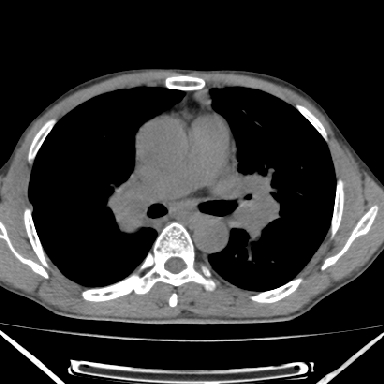

以下是引用zjzjr在2007-3-23 17:24:00的发言:[br]双侧肺门淋巴结明显肿大,以左侧为著,支气管受压变窄,肺内可见结节状及絮状高密度影,边缘模糊.考虑淋巴瘤肺内浸润.